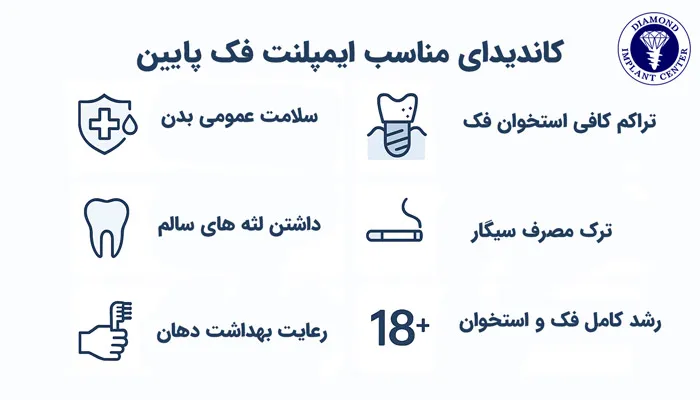

کاندیدای مناسب برای جراحی ایمپلنت فک پایین

کاندیدای مناسب برای جراحی ایمپلنت فک پایین افرادی هستند که شرایط دهانی و جسمی مناسبی برای پذیرش این درمان داشته باشند، برخی ویژگی های مهم عبارتاند از:

- بیمار نباید دچار بیماری های کنترل نشدهای مانند دیابت شدید یا مشکلات سیستم ایمنی باشد.

- تراکم و حجم استخوان فک پایین باید به اندازهای باشد که بتواند پایه تیتانیومی را محکم نگه دارد و در صورت تحلیل استخوان، پیوند استخوان لازم است.

- لثهها باید بدون عفونت و بیماری های پیشرفته پریودنتال باشند.

- سیگار میتواند روند جوش خوردن ایمپلنت با استخوان را مختل کند.

- فرد باید توانایی و انگیزه کافی برای رعایت بهداشت دهان و دندان را داشته باشد.

- افراد باید رشد فکشان کامل شده باشد؛ معمولا بالای ۱۸ سال.

علاوه بر این موارد، افرادی که دندانهای پایین آنها بهدلیل پوسیدگی شدید یا شکستگی غیرقابلترمیم نیاز به کشیدن دارند نیز میتوانند کاندید مناسبی برای ایمپلنت فک پایین باشند. بیمارانی که از دندان مصنوعی متحرک استفاده میکنند و از لق شدن یا ناپایداری آن ناراضی هستند نیز معمولا گزینههای بسیار خوبی برای ایمپلنت محسوب میشوند، زیرا فک پایین به دلیل تراکم استخوانی بالاتر، پایداری بیشتری برای ایمپلنت فراهم میکند. همچنین کسانی که قصد انجام ایمپلنت کامل فک را دارند، در صورتی که سلامت عمومی و استخوانی آنها مناسب باشد، میتوانند بهترین نتیجه را از این درمان دریافت کنند.